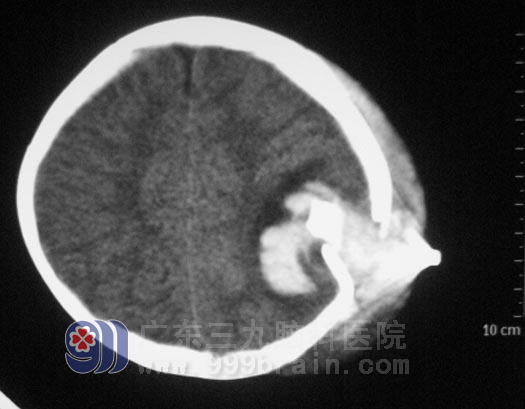

还不到两岁的冰冰,聪慧可人,正在玩耍时意外被木棍打到头上,摔倒在地,随即出现呕吐、意识障碍,急送当地医院,头颅CT检查提示:左侧顶骨凹陷性骨折,轻度大脑镰下疝,左侧顶叶挫裂伤并血肿,左侧顶部硬脑膜下出血。

入院时冰冰呈昏迷状,双侧瞳孔不等大,左侧颞顶部头皮肿胀明显。鲁明主任详细了解病情及查阅影像资料后,急诊在全麻下行左侧颞顶脑挫裂伤灶+血肿清除术+左侧颞顶颅骨碎骨取出+凹陷性骨折整复术。术中见左侧颞顶部肿胀明显,切开头皮见冒状腱膜下有积血,逐渐分离骨膜至骨折处,大量黑色不凝血性液体喷出;完全分离骨膜和帽状腱膜后见颅骨凹陷处脑组织及淤血膨出,在显微镜下彻底清除血肿及坏死脑组织。术后的她恢复很快,语言、肢体运动等功能均没有受到影响。